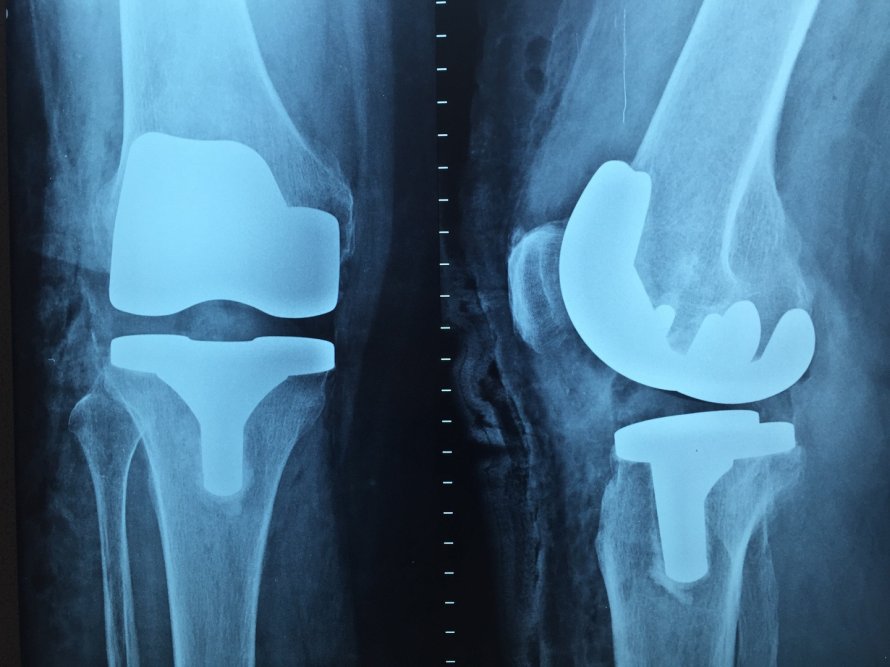

Военные испытывают постоянную нагрузку на стопы и позвоночник. Жёсткая обувь и многокилометровые марши приводят к искривлениям и артритам.